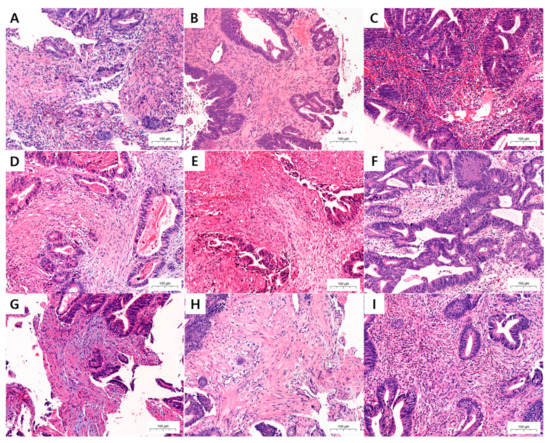

HE-stained PBSs were evaluated for neoadjuvant therapy response, ITB, KM grade, TSR, and DR (Figure 1). Neoadjuvant treatment response was evaluated with Dworak classification, and divided into good responder (grades 3 and 4) and poor responder (grades 0, 1, and 2). In addition, ITB was assessed in PBSs using pancytokeratin immunohistochemical staining (IHC) (Figure 2). Two pathologists (K.Y. and K.J.S.) independently assessed all pathological parameters; if any disagreement occurred during this process, it was revolved by consensus, which was reached by meeting with a third pathologist (Y.C.).

TB has traditionally been defined as isolated single cancer cells or <5 cancer cells in the invasive front [5]. Some authors renamed the traditional TB concept as peritumoral budding and newly defined ITB if TB is detected at the center of the tumor (Figure 1A,B) [5,22].

2.6. Desmoplastic Reaction Classifications

DRs were classified into immature, intermediate, and mature types [19,20,21]. The immature DR type was selected if myxoid stroma, with a basophilic or amphophilic amorphous mucinous substance, was present. The intermediate DR type was characterized by the absence of a myxoid stroma and the presence of keloid-like collagen, which was observed as a thick bundle of hypocellular collagen with bright eosinophilic hyalinization. Finally, if a myxoid stroma and keloid-like collagen were both absent, the DR was classified into the mature type. The mature DR was composed of multiple fine mature collagen fibers [19,20,21] (Figure 1). We searched all fields with low-power field (LPF), and then selected a hotspot. When myxoid stroma or keloid-like collagen was recognized with certainty, we defined them as being present, regardless of the smallness of their area.

2.7. Klintrup–Mäkinen Grade

Originally, the KM grade was designed to evaluate the tumor invasive margin of surgical specimen. However, biopsy samples usually do not include an invasive front; and even if there was one, it would be impossible to detect it in biopsy samples. Therefore, we scanned all fields of the HE slide using LPF, and then selected a hotspot. Finally, we determined the KM grade in a 200× hotspot.

KM grade is scored semi-quantitatively using a four-grade scale. A score of 0 was given when there was no increase in the number of inflammatory cells; a score of 1 denoted a mild and patchy increase in inflammatory cells, but no destruction of invading cancer cell islets by the inflammatory cells; a score of 2 was given when inflammatory cells formed a band-like infiltrate, with some destruction of cancer-cell islets; and a score of 3 denoted a prominent inflammatory reaction, forming a cup-like zone, with frequent destruction of cancer-cell islets [14]. The KM grade is often split into two categories: weak (0 and 1) and strong (2 and 3) [15,16] (Figure 1).

2.8. Tumor–Stroma Ratio

The TSR was designed to be scored by assigning a percentage of the proportion of tumor-associated stroma present at the invasive tumor front in a 200× high-power field (HPF) in surgical specimens. We evaluated the TSR in PBSs in the same way as we did the KM grade, which is scanning the all fields then selecting hot spot. The TSR is dichotomized into low (≤50% stroma) and high (>50% stroma) types [16,18] (Figure 1).

Figure 1. Representative microscopic images of tumor microenvironmental (TME) factors in the pretreatment biopsy samples (PBSs) of colorectal carcinoma (CRC). (A) High- and (B) low-grade intratumoral budding (ITB). (C) Strong and (D) weak grade Klintrup–Mäkinen (KM) grade. (E) High and (F) low ratio of tumor–stromal ratio (TSR). (G) Immature, (H) intermediate, and (I) mature type of desmoplastic reaction (DR). (AI, HE staining; 200×).